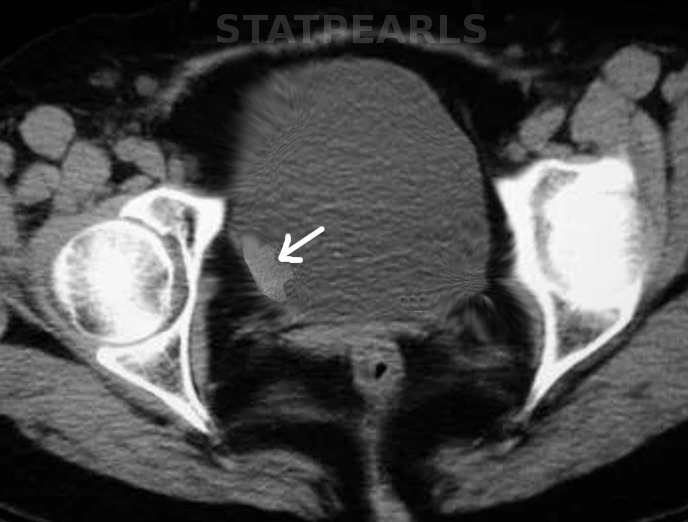

Bladder Cancer

圖1: 膀胱癌。圖片由 S Bhimji MD 提供